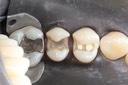

Photos of Clinical Operations

Mentors: Drs. Randy Allan, Greg Card, Peter Kearney

Clubs #44 and #50 joint meeting